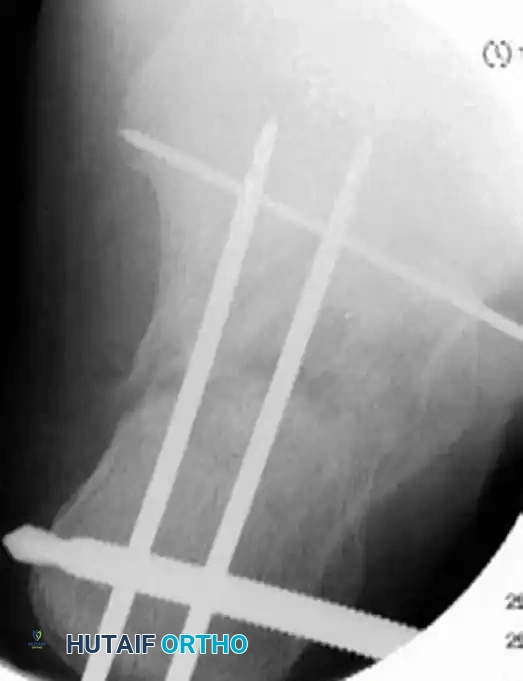

- Insert multiple smooth Kirschner wires (K-wires) from the lateral aspect of the calcaneus, directing them medially into the dense bone of the sustentaculum tali.

- Verify the position of the K-wires using axial and Broden’s fluoroscopic views to ensure they do not penetrate the subtalar joint or the medial neurovascular bundle.

- Place 3.5-mm or 4.0-mm partially threaded cortical screws over the provisional K-wires. These screws are directed from lateral to medial, compressing the lateral articular fragment against the medial sustentacular fragment.

- To maintain the corrected position of the tuberosity, insert fully threaded screws from the posterior tuberosity directed anteriorly toward the calcaneocuboid joint, parallel to the initial Steinmann pin. Fully threaded screws are preferred here to act as position screws, preventing loss of calcaneal length.

- Perform a final fluoroscopic check to confirm extra-articular hardware placement, restoration of Böhler’s angle, and correction of varus alignment.